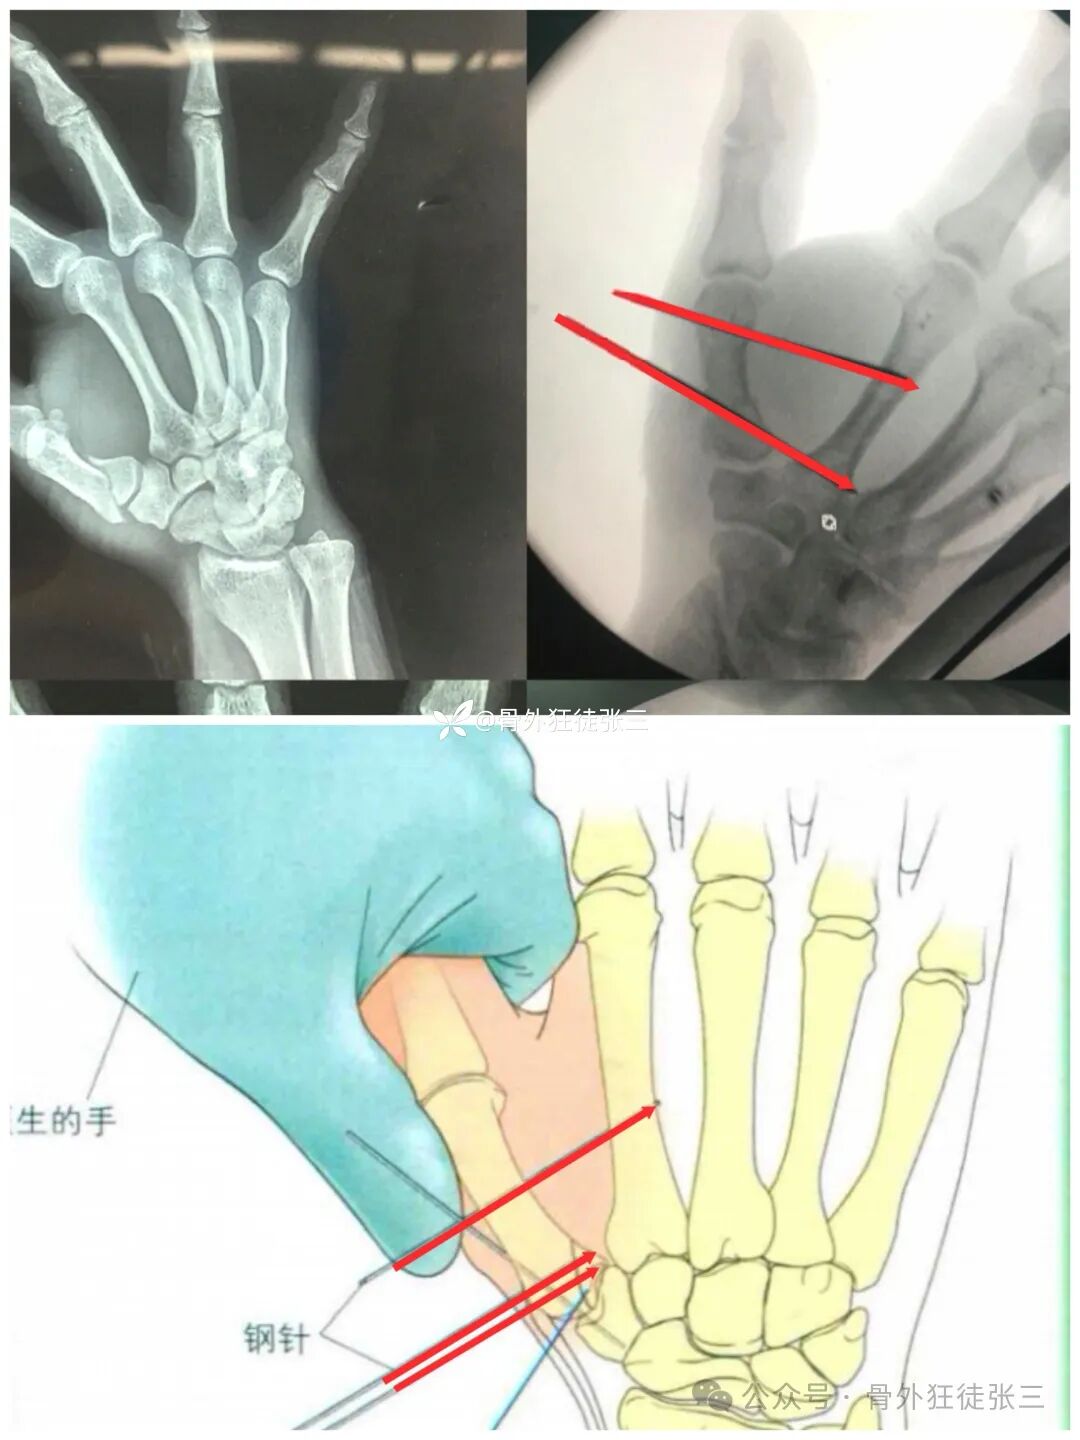

经皮闭合复位,横向克氏针固定于第二掌骨+斜针固定第一腕掌关节,书上甚至用了两枚细螺钉。

固定方式,采用经皮复位。两枚克氏针(Iselin技术)横向固定,不固定关节,书上原图有一枚斜针固定第一腕掌关节,针尾可以交锁使用小针夹或者骨水泥或者弹力手套等。

个人经验针尾直接折弯可把第二掌骨作为克氏针支架的横杆,足够牢固,针尾再次锁定,意义不大。